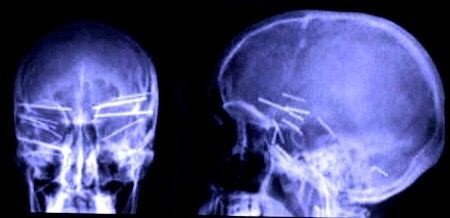

4. 自杀失败,头骨钉枪打进12根钉子的人

这张图应该够恐怖了。这名美国奥勒冈州的男子在2006年求医,原因是“头有点痛”。直到医生从X光发现他头盖骨钉着12根钉子,当时33岁的男子才承认自己是想用钉枪自杀。后来呢?医生帮他把所有钉子拔出来,这名男子又继续活着了。